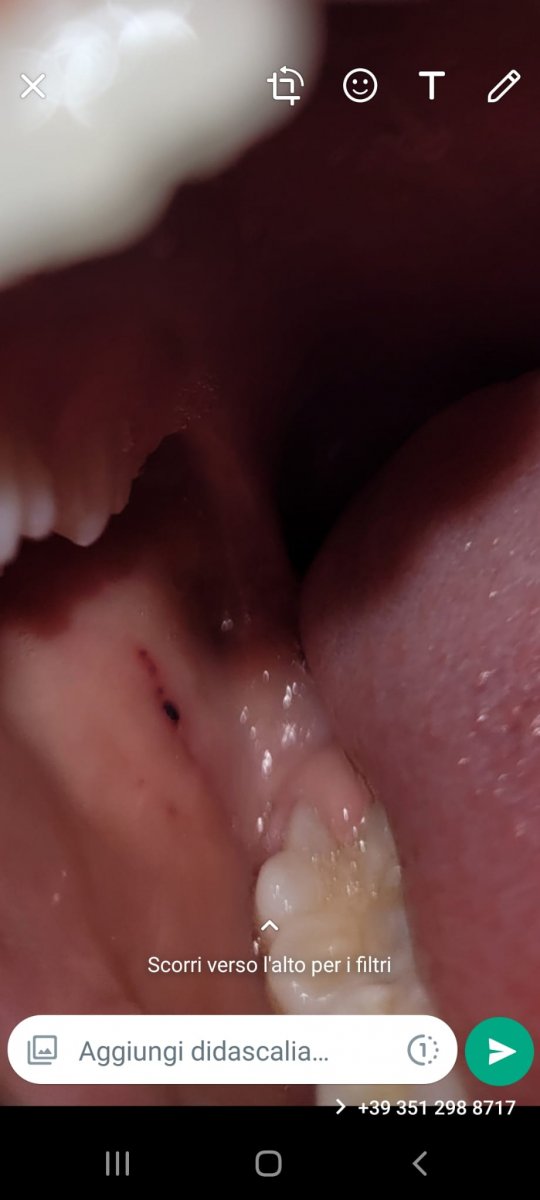

Salve professore ho notato questa macchiolina nera nella bocca di mia figlia di 6 sono preoccupato può darsi che sangue raggrumato grazie mille spero che non sia niente di grave

2300F3FD-C429-4326-9767-5E27F799961B.jpeg

Emorragia post traumatica, si riassorbe da sola.